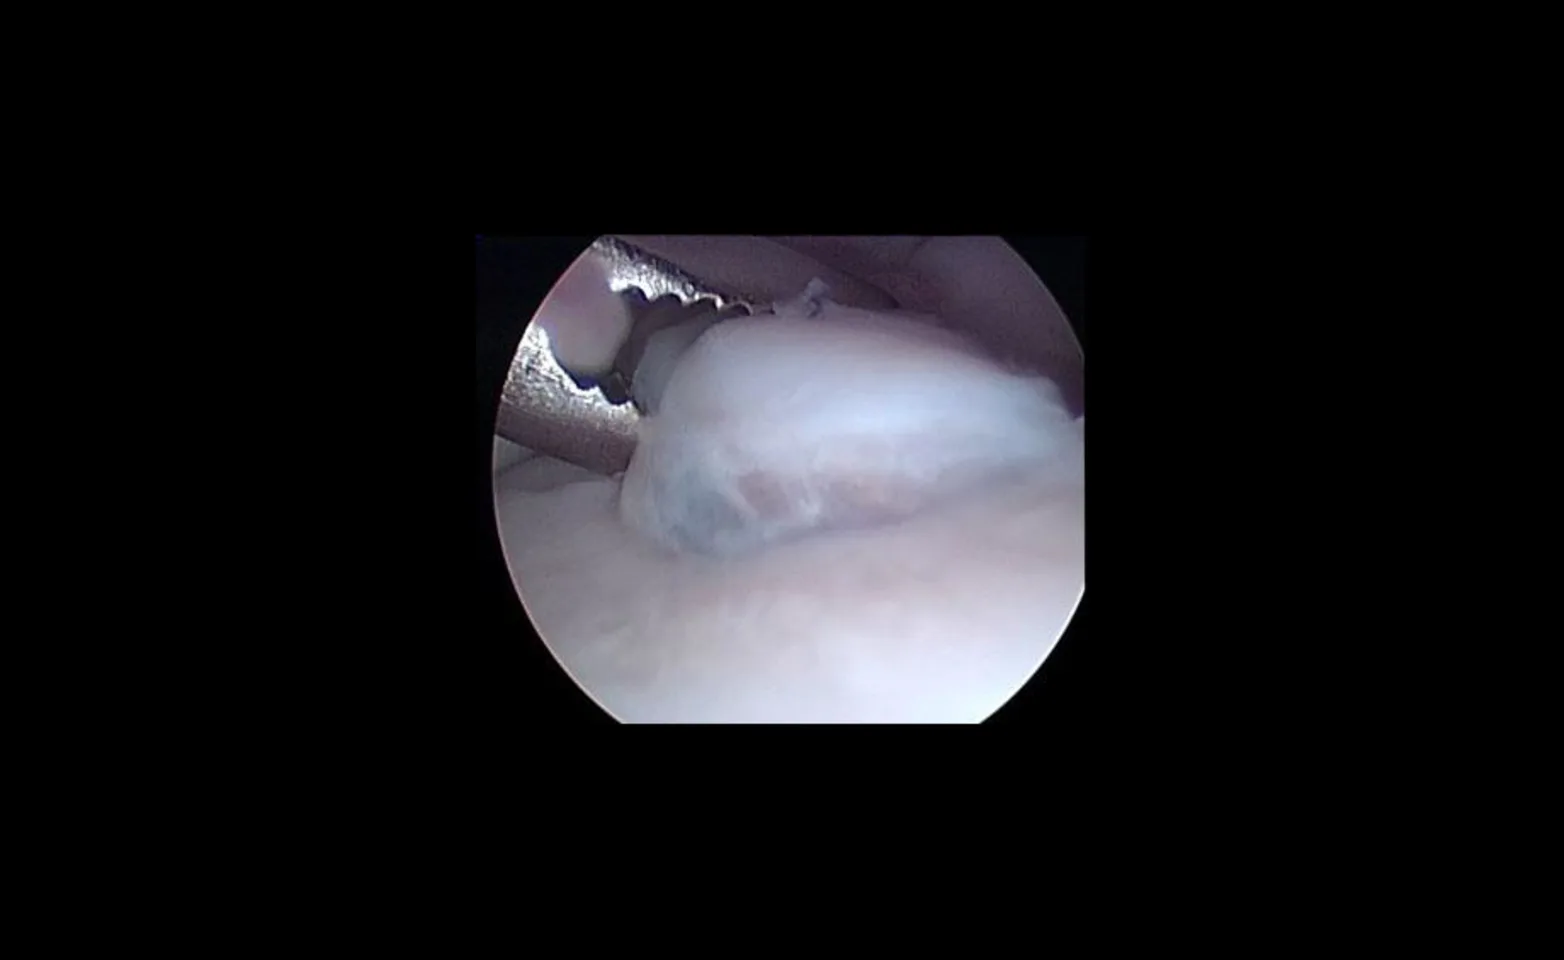

Arthroscopic view of a grasping instrument removing a large fragmented coronoid process within the elbow joint of a dog.